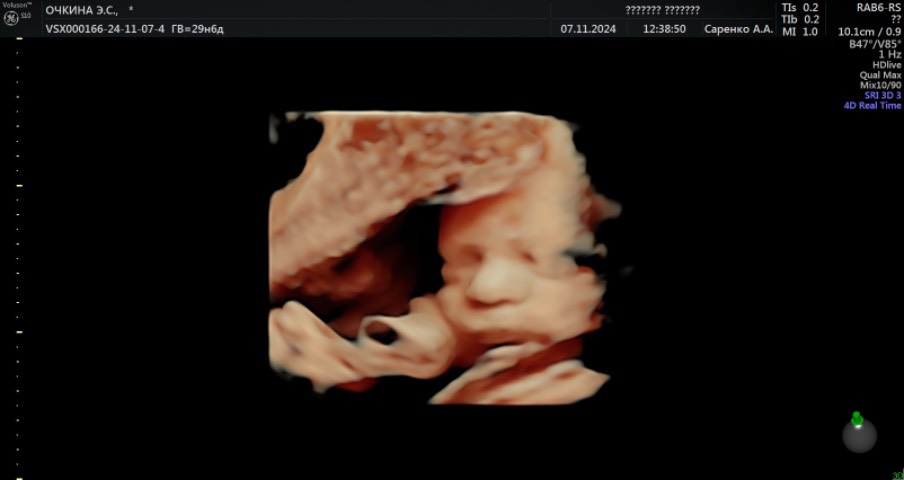

Девочки, сегодня была на 3-м скрининге + 3Д и 4Д. Эмоции зашкаливают. Даже всплакнула. Ну что за милая мордашка😍 Отворачивался, не хотел личико показывать) Покидайте своих малышей!) Отдельно, беременняшкам Оренбурга и региона хочу порекомендовать доктора-узиста Саренко! Настоящий профессионал💪🏼

Сегодня тоже была на 3д узи +скрининг. Эмоции даже описать не могу, это счастье.... Счастье, что здоров, счастье, что он есть! Лёгкой беременности вам!